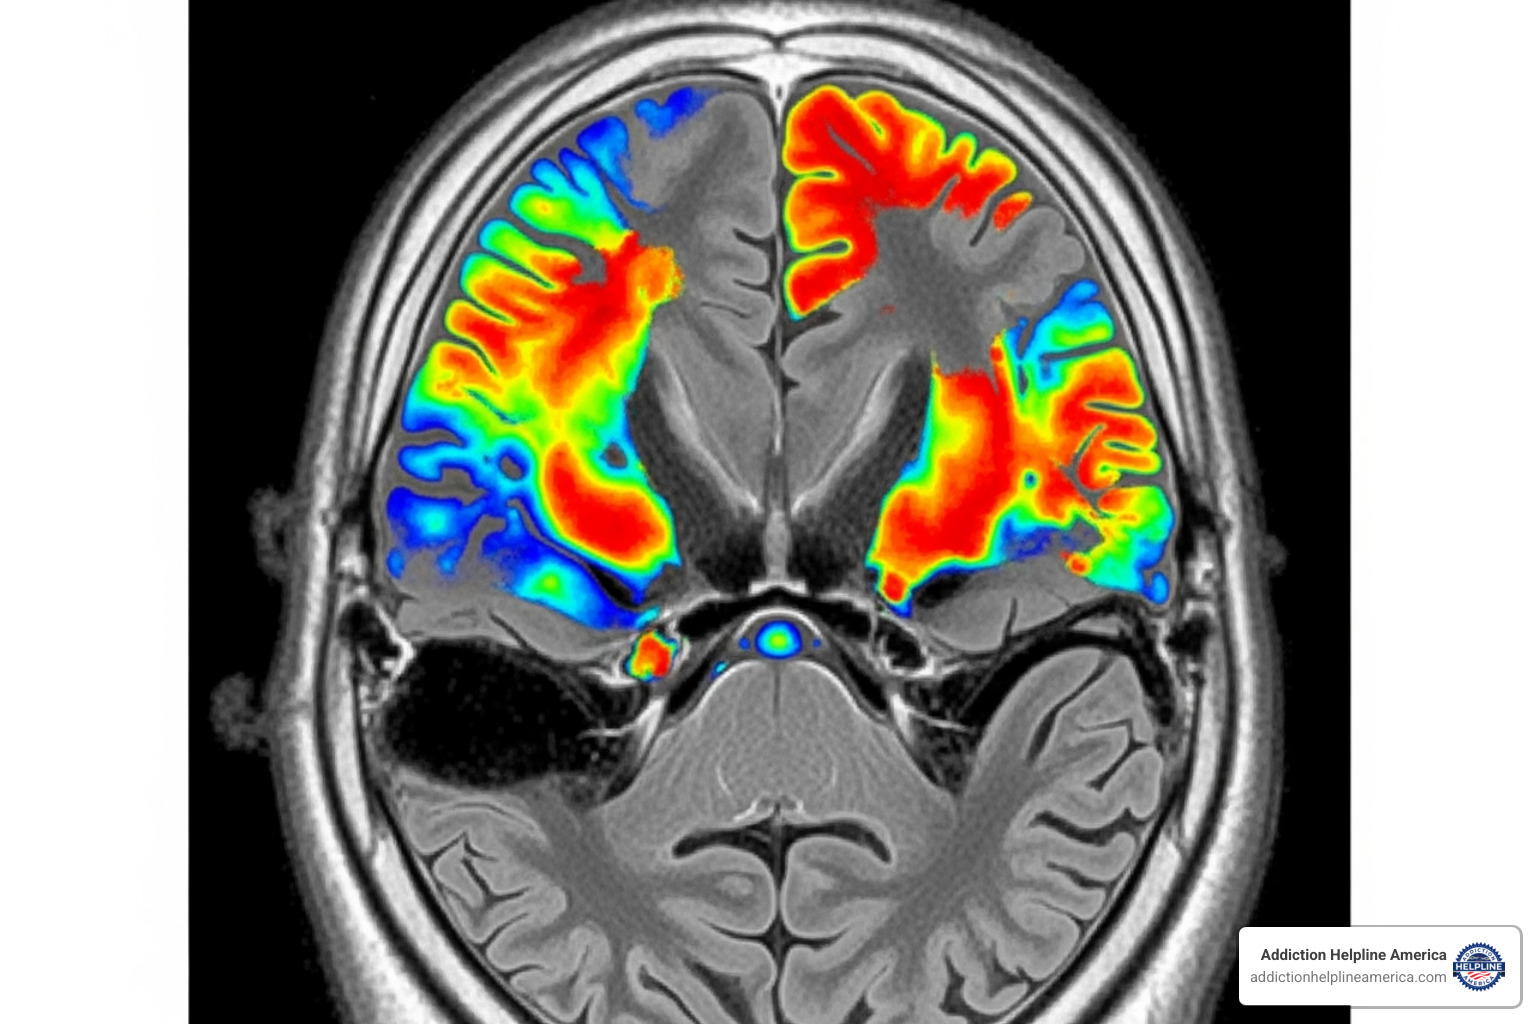

Cannabis Use Disorder is a mental health condition classified as mild, moderate, or severe depending on the number of symptoms. It develops when THC (Tetrahydrocannabinol), the main psychoactive compound in marijuana, hijacks the brain’s endocannabinoid system, which helps regulate mood, memory, and pleasure.

THC triggers a flood of dopamine, the “feel-good” chemical. With repeated use, the brain adapts, becoming less sensitive to its own dopamine. This leads to tolerance—needing more marijuana to get the same effect. Eventually, the brain depends on THC to function normally, leading to physical dependence. When this is combined with a powerful psychological craving, it becomes an addiction.